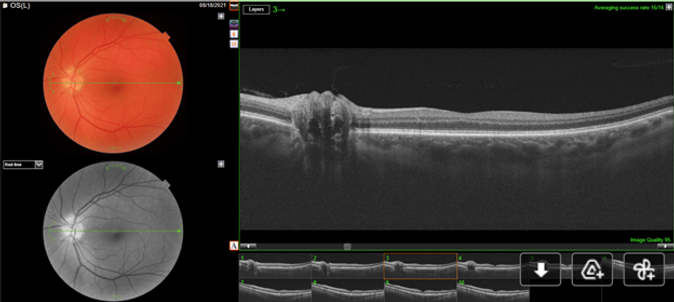

SS-OCT’s over the macula and optic were performed in the right and left eye, and are shown below:

Question: Based on the above SS-OCT scans, what abnormality can be seen?

Question: Is this a case of pseudo-papilledema or papilledema?